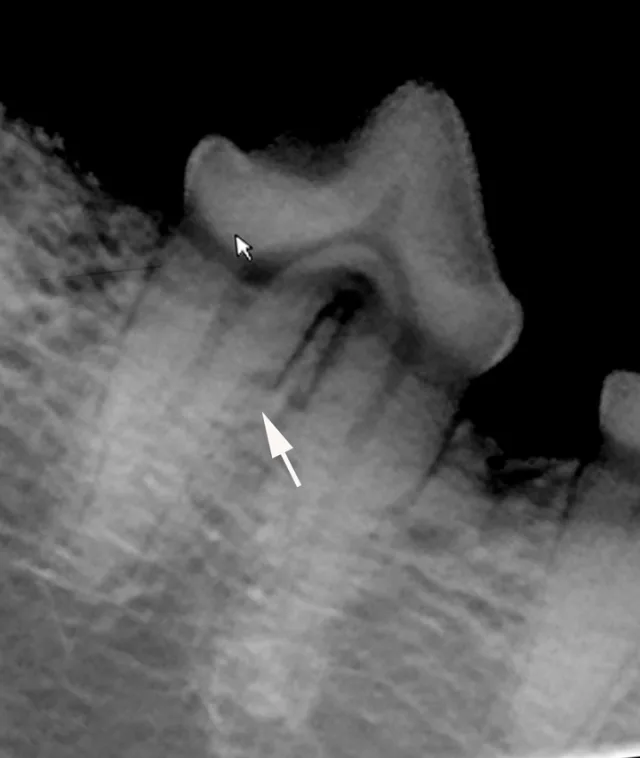

Resorption of the right maxillary canine root in a 3-year-old English bulldog.